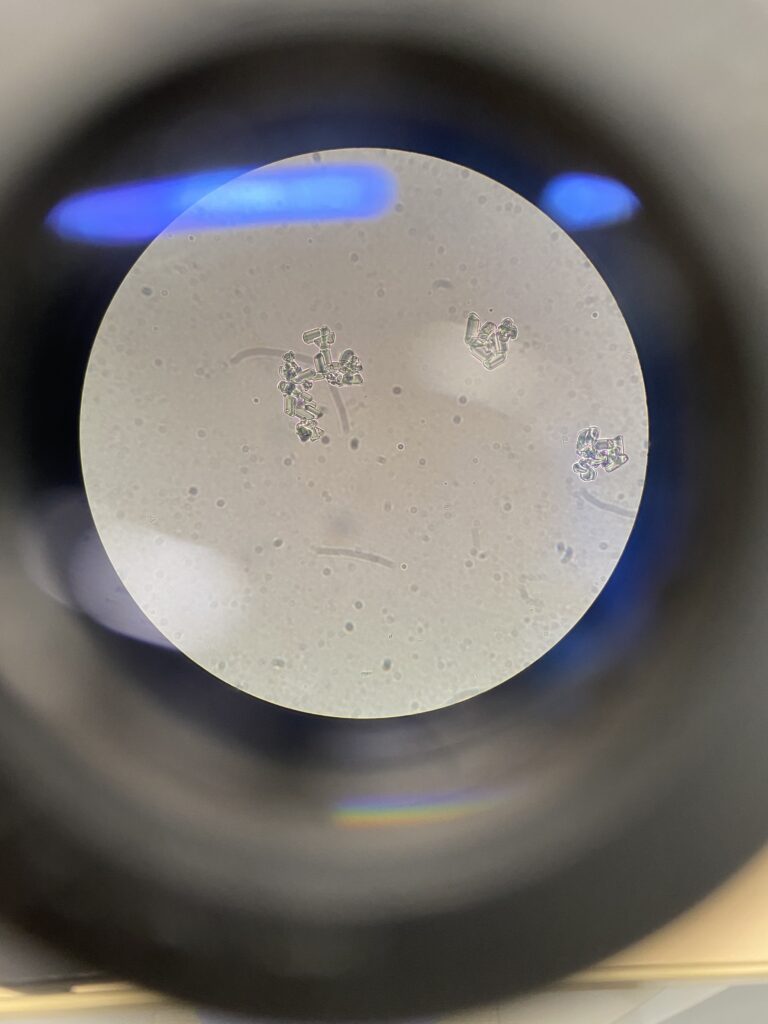

尿を顕微鏡で見たところです。長方形に見えるのが結石の成分である結晶です。

尿検査でこのように結晶を見つけることができればすぐにエコー検査をして膀胱や腎臓に結石がないか確認します。

結石がなければ結晶が出ないように工夫をすることで膀胱結石が悪化することを早期に予防できます。